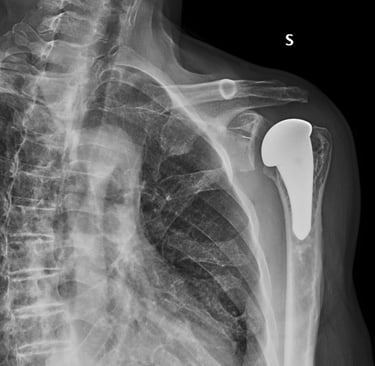

Artrosi di spalla (Gleno-Omerale)

Gallery

Attività Chirurgica